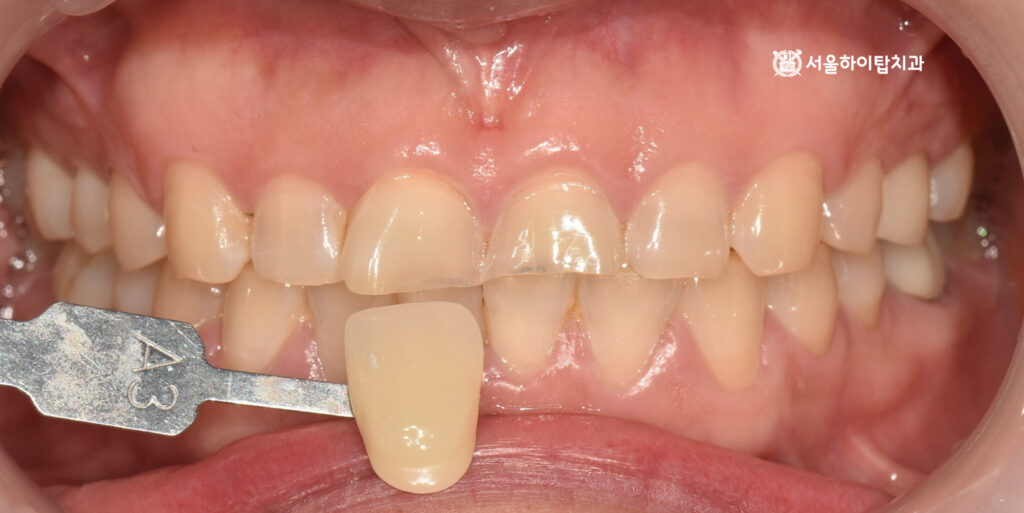

이후 쉐이드 테이킹을 통해 주변 자연치와 어우러지는 색상을 선택해 주고

최종 크라운이 올라갈 수 있게 형태를 알맞게 프렙(prep) 해주게 됩니다.